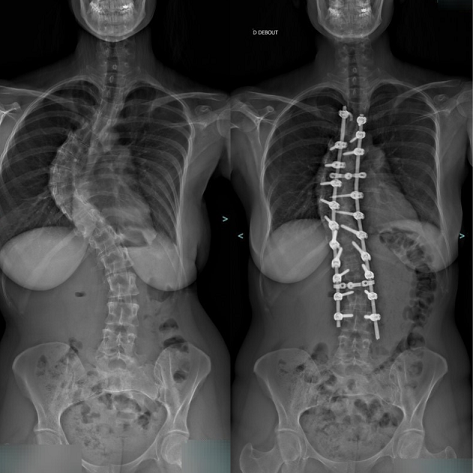

L'intervention consiste à placer une instrumentation métallique comportant une tige, des vis, ou agrafes au contact de la colonne vertébrale afin de corriger la déformation dans les trois plans de l'espace, tout en restaurant les équilibres.

Souvent, le redressement obtenu n'est que partiel compte tenu de l'importante raideur de certaines portions des courbures.

Néanmoins, même une correction partielle et surtout l'évitement de toute reprise évolutive future sont suffisants pour améliorer l'avenir fonctionnel, en comparaison avec une évolution non traitée.

- La correction des courbures s'effectue en redressant progressivement les tiges amarrées à la colonne. Des contrôles radiographiques vérifient la bonne position des implants.